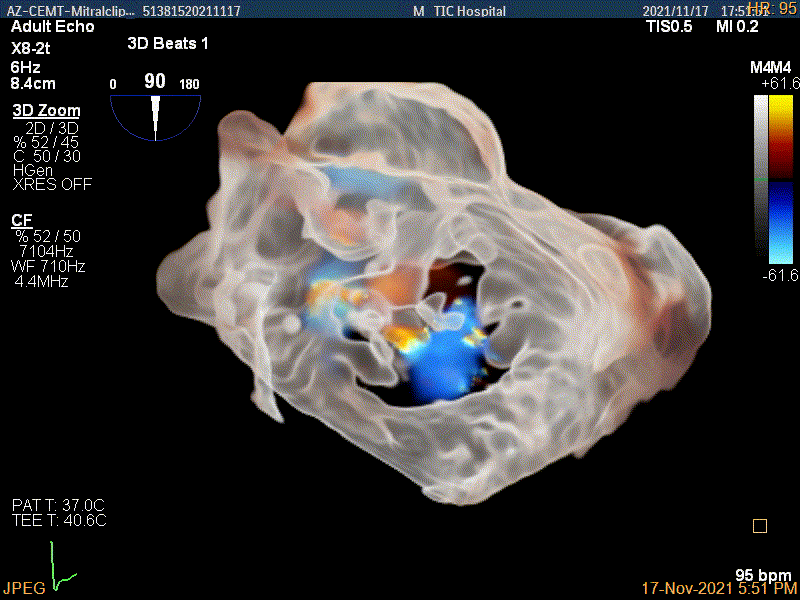

3D-color MV view:源自于交界区的大量反流

3Dcolor证实残余分流主要来源于残余脱垂

3D-color视图下两个夹子间少量残余反流